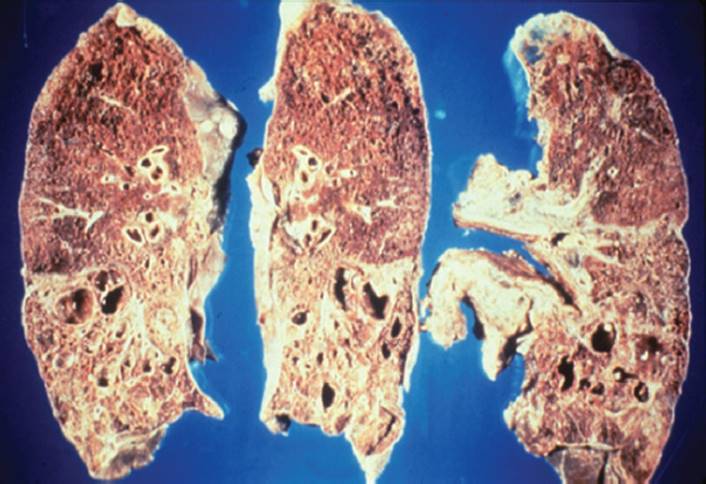

CF is the most common autosomal recessively inherited disorder in Caucasians.69 Within the lungs, this genetic defect leads to excessive production of thick, dehydrated, hyperviscous mucus and impairment of the mucociliary blanket.70,71 The incidence is 1 in 3,000 births in the United States and Europe. Chronic bouts of inflammation and infection lead to the breakdown of protein in the lungs. Obstructions of small airways develop from mucus plugs and destruction of the cartilaginous support of the airways. The end result is bronchiectasis, which is a permanent dilatation of the bronchi that is characterized by inflamed airways, which are full of purulent sputum23 (see Figs. 7-11and 7-12).

FIGURE 7-12 Cystic fibrosis. This gross pathology slide clearly illustrates destruction of the parenchymal tissue and the large cyst formation. (Courtesy of Dana Gryzbicki, MD, University of Pittsburgh, PA.).